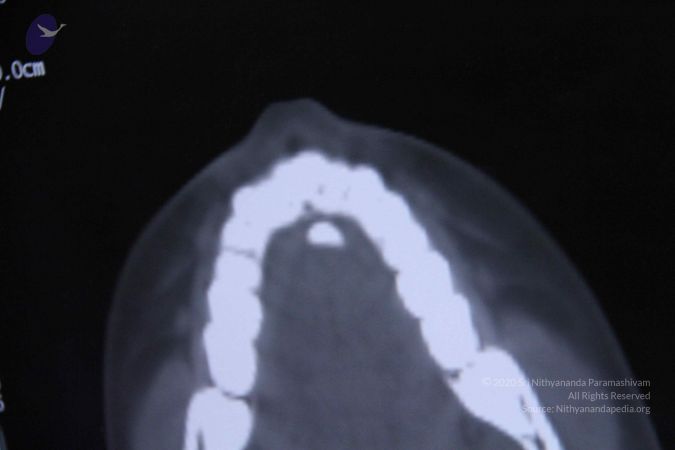

Scientific Validation of Materialization The most significant in a series of studies conducted by the research team were the tests done on Poornima (Ma Nithya Mahayogananda), a young entrepreneur and Paramahamsa Nithyananda’s energy channel from Singapore. On 6th September 2011, three different studies were conducted during a 4-hour session, in which Paramahamsa Nithyananda materialized a variety of objects through this individual, including sacred ash and precious stones. The studies were: 1) Whole body baseline CT scan of the subject Baseline whole-body CT scans proved the absence of any hidden objects in the body and vicinity of the subject. After the energy transfer from Paramahamsa Nithyananda to the subject, a repeat scan clearly shows the sudden appearance of a radio-opaque foreign body in the oral cavity without any delay or repositioning. The recording of the spiral CT after materialization revealed the presence of materialized objects both in sections and 3D format. 2) Simultaneous qEEG of Paramahamsa Nithyananda and the subject The qEEG recording of both Paramahamsa Nithyananda and the subject done during the process of energy transfer clearly showed ‘Entrainment’ (Synchronicity) in the brain waves of both individuals during the process of materialization, proving that a process of attunement was indeed taking place at the time